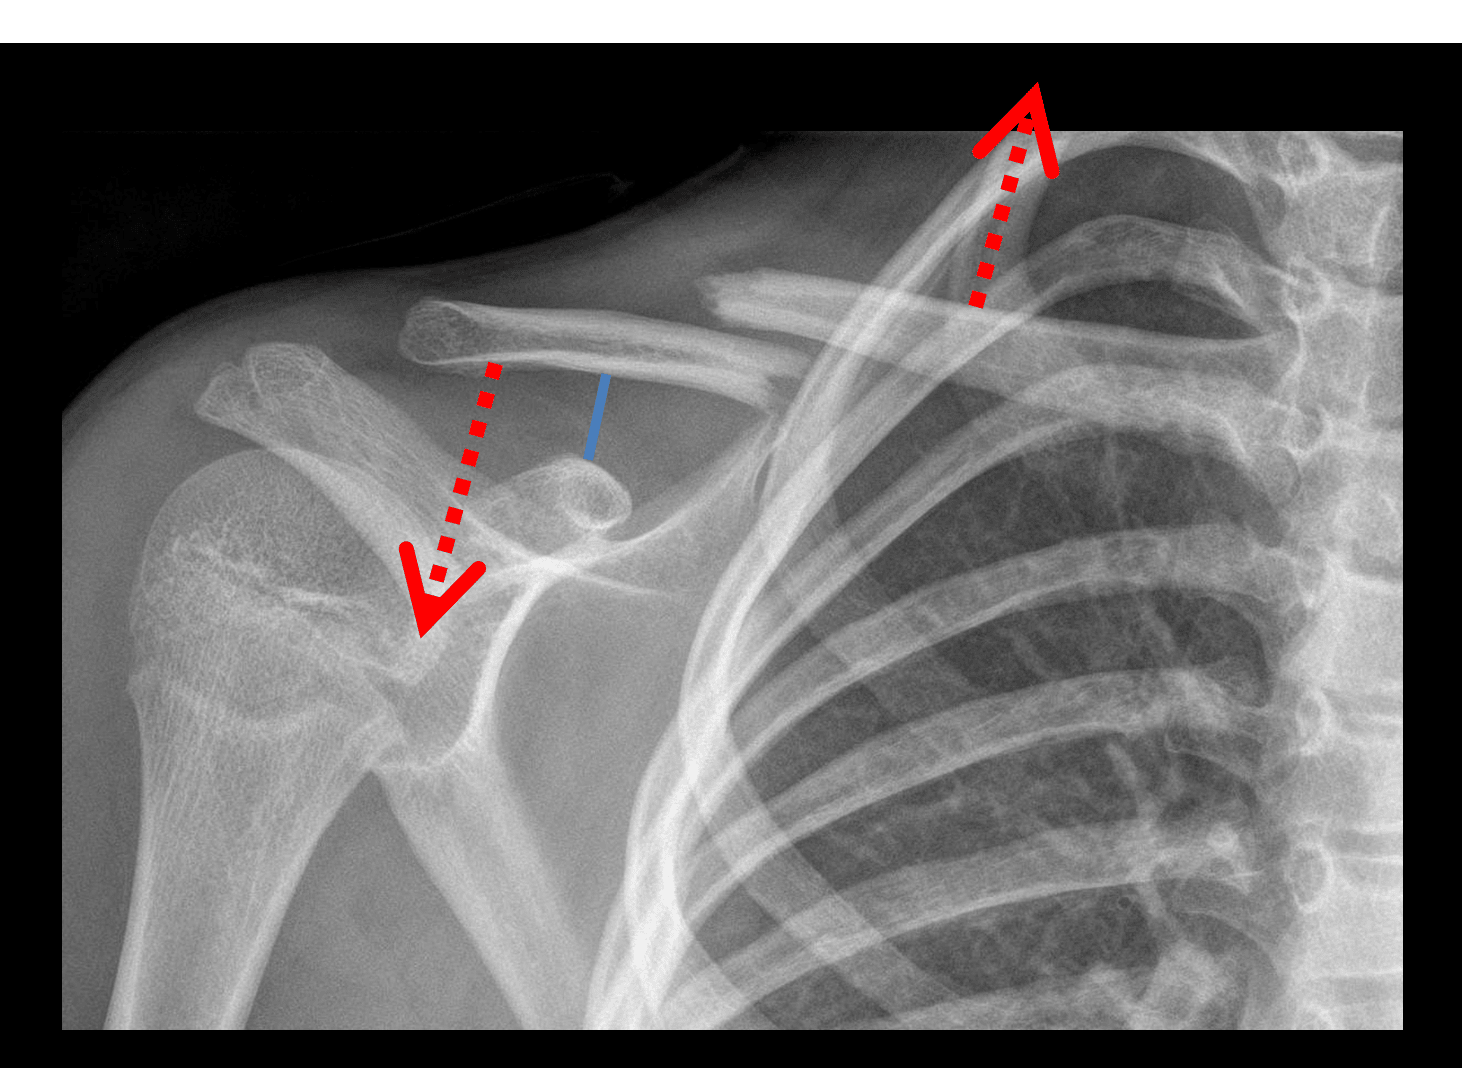

• Acute right clavicle fracture between the middle and distal thirds with 2 cm override and approximately one shaft width superior displacement of the proximal fracture fragment

Acute right clavicle fracture between the middle and distal thirds with 2 cm override and approximately one shaft width superior displacement of the proximal fracture fragment.

No widening of the acromioclavicular joint or coracoclavicular distance.

• When the fracture is complete, the medial fragment is typically pulled superiorly (and posteriorly) by the sternocleidomastoid muscle while the lateral fragment is pulled inferiorly (and anteriorly) by the weight of the arm

• Always look for associated acromioclavicular joint malalignment or widening of the coracoclavicular distance (normal measurement < 13 mm)

Red arrows: upward pull on the medial fracture fragment by the SCM and downward pull on the lateral fragment by the weight of the arm. Blue line: normal coracoclavicular distance